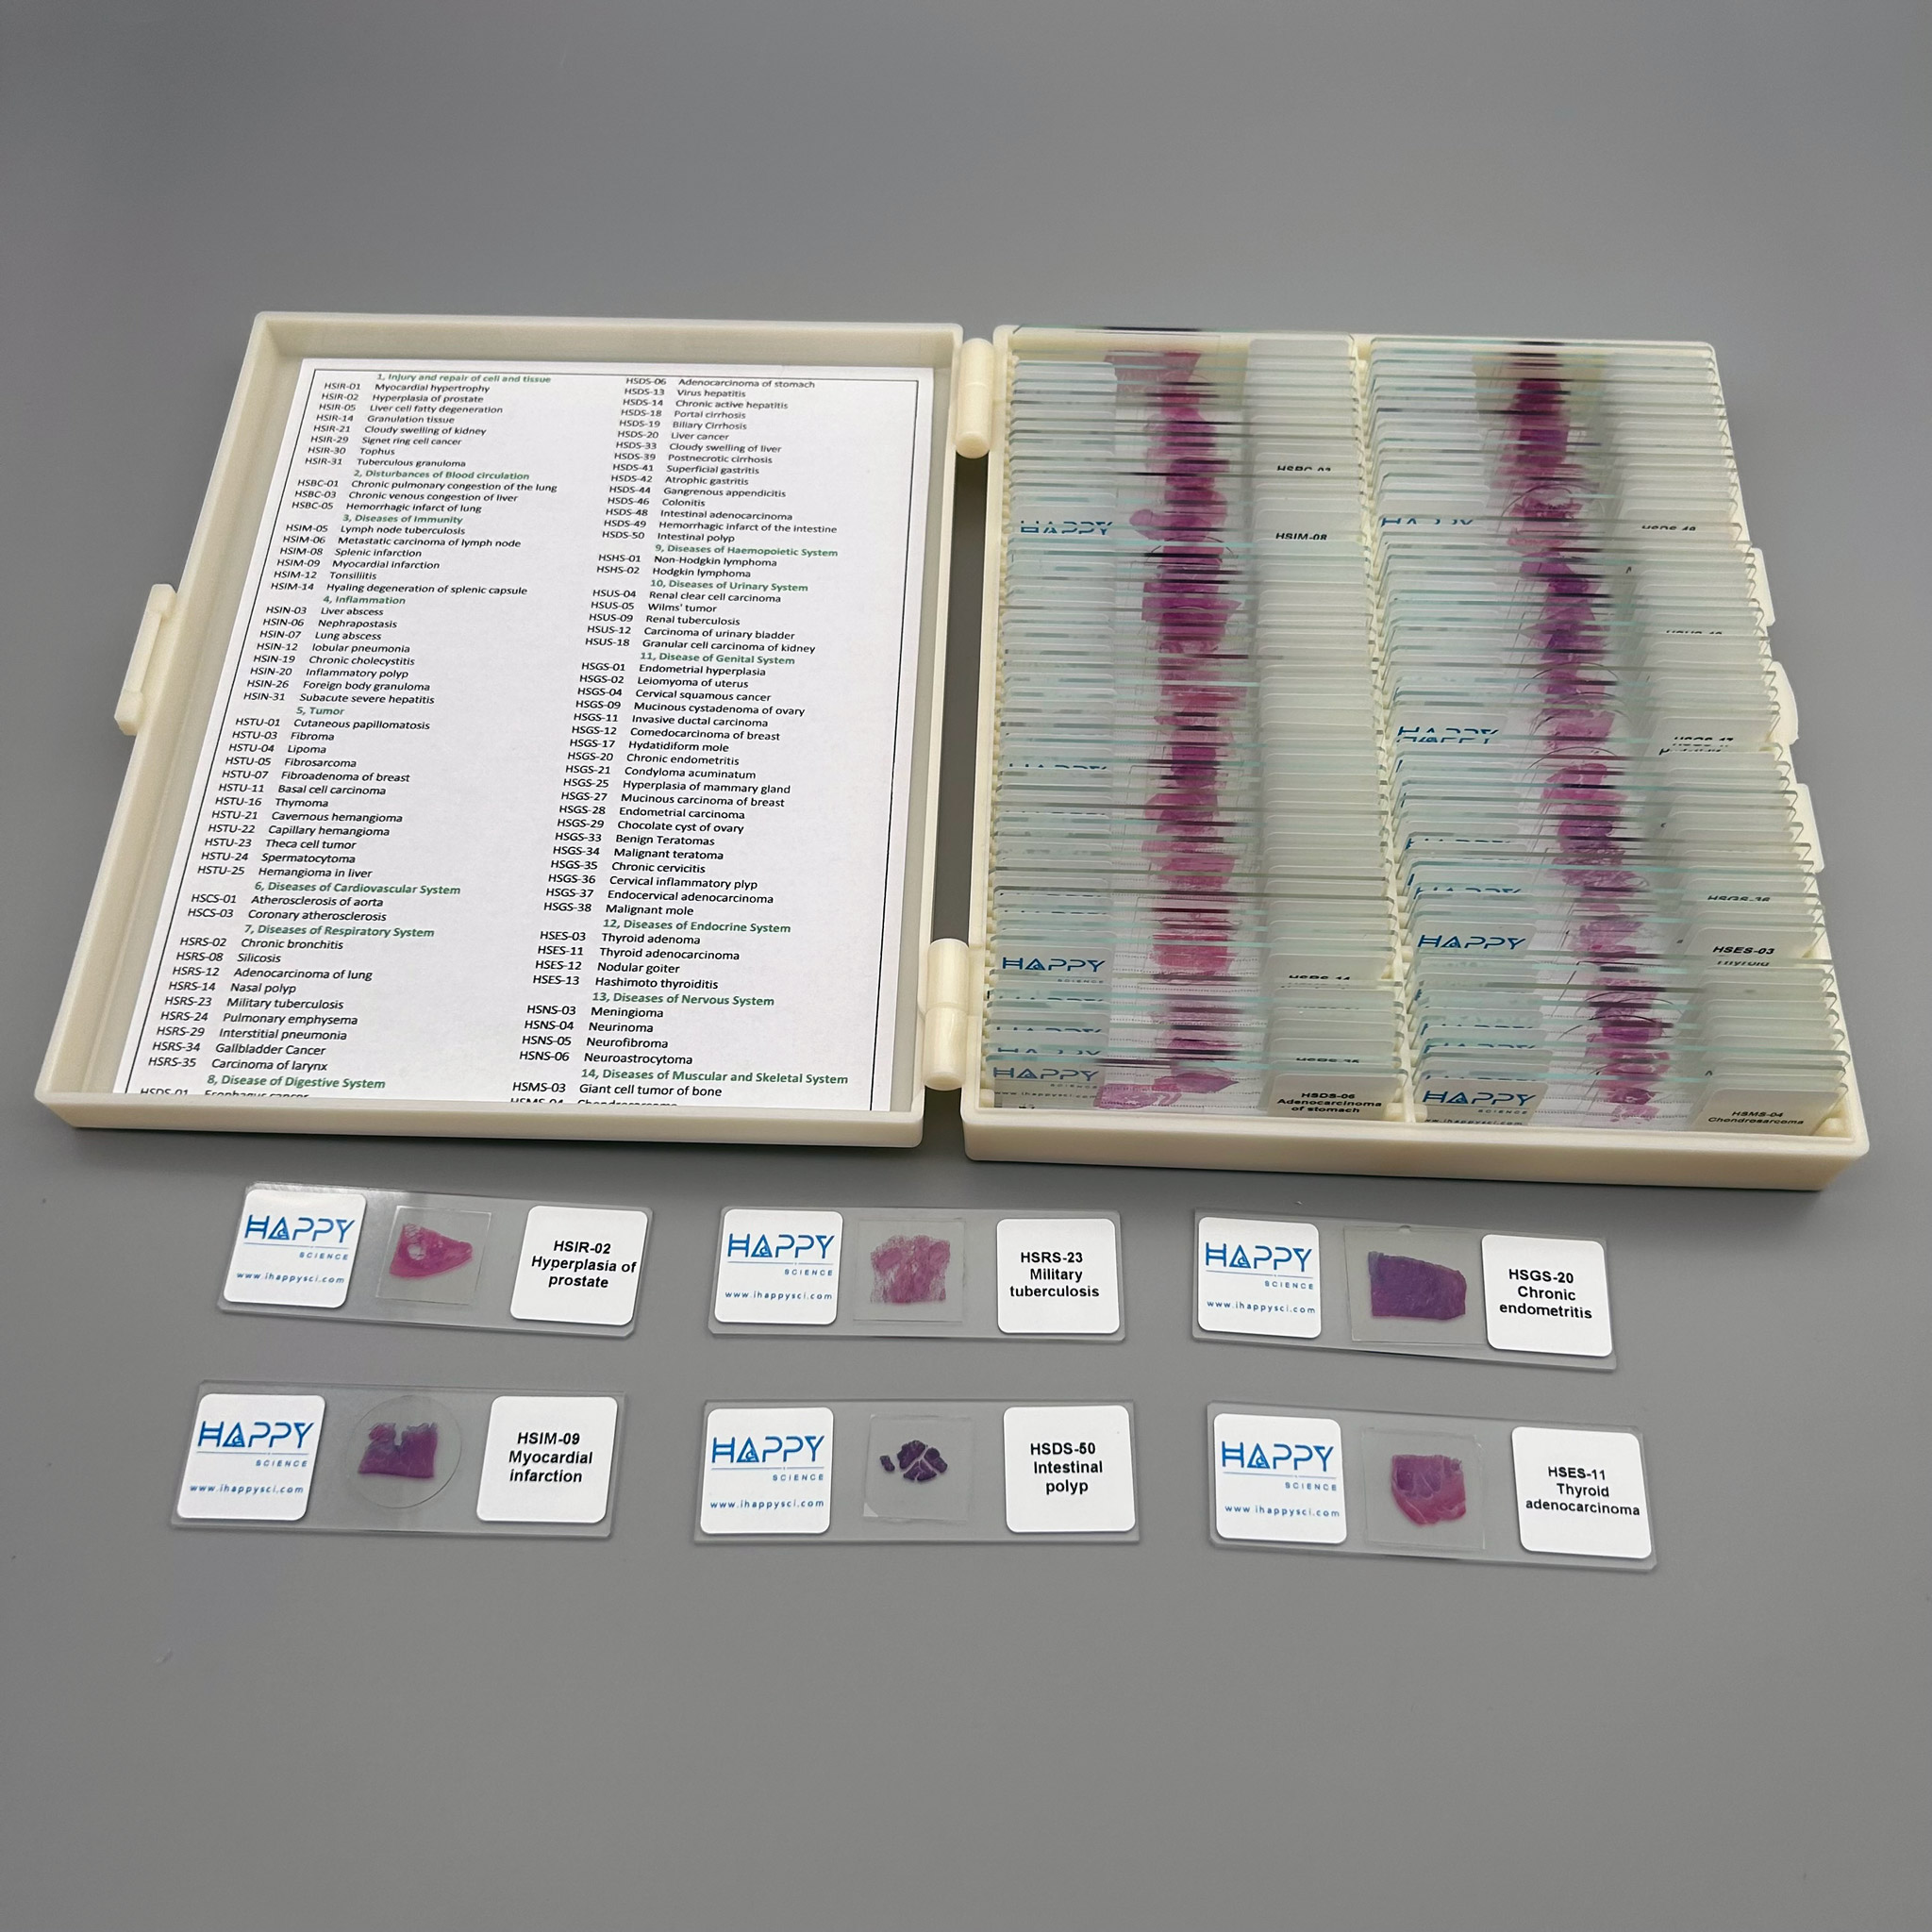

Advanced 100pcs human pathology teaching slides wholesale, university standard, Factory Outlets

Pathology teaching slides

14 system of the human body

Individually labeled

Recommend to: doctors, teachers and students

Advanced 100pcs human pathology teaching slides wholesale, university standard, Factory Outlets

The Pathology teaching slides we offer are professionally hand-mounted, accurately stained, and individually labeled. Our microscope pathology slides are great for medical students, It has an excellent introduction to human disease in microscopy. The Pathology teaching slides are cover-slipped and preserved in cedarwood oil. All slides are carefully labeled for easy reference and are arranged in a fine plastic box with a separator. This pathology teaching slide set includes 14 systems of human diseases. It is excellent for educational use and is perfect for all levels of medical student study including home school programs.

What’s included in this 100pcs pathology teaching slides set: